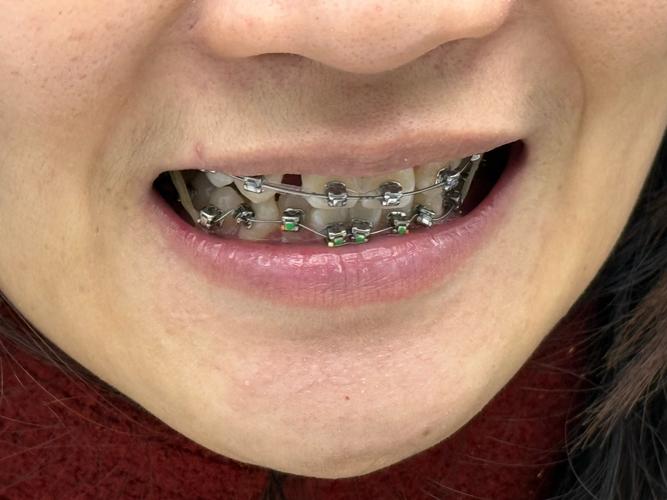

| 固定矫治器+螺旋弹簧 | 在固定托槽(如金属托槽、陶瓷托槽)间植入螺旋弹簧,通过弹簧弹力推开牙齿。 | 单颗或多颗牙间隙不足,需精准控制牙齿移动方向。 | 优点:力量可控,适用范围广;缺点:口腔卫生维护难度增加,需定期复诊调整。 |